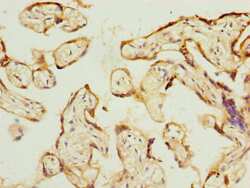

- Immunohistochemical analysis of PSG3 in paraffin embedded human placenta tissue using a PSG3 polyclonal antibody (Product # PA5-98411) at a dilution of 1:100.